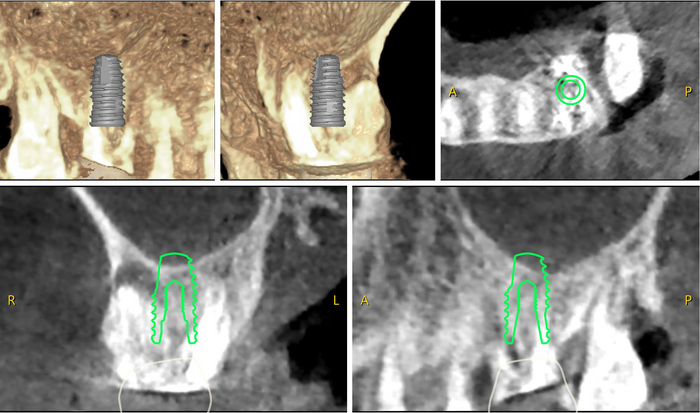

VAROGuide Fabrication

VAROGuide Fabrication using VARO Plan